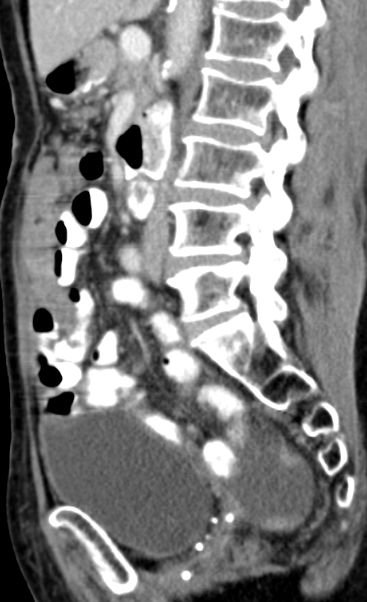

Rezidiv eines serösen Ovarialkarzinoms. Großer Tumor im Leberhilus, intrahepatische Herde. |

Pfortader frei. | |||